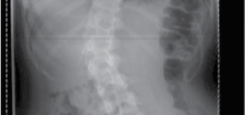

Clinical & Radiographic Imaging Archive